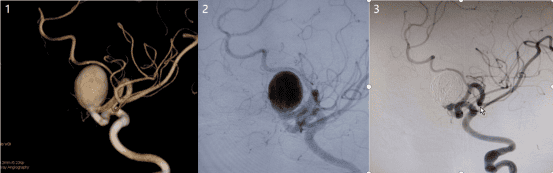

血流导向装置治疗颅内巨大动脉瘤。

国际前沿技术血流导向装置治疗巨大颅内动脉瘤具有安全、有效、低复发率优势。

图

1动脉瘤三维重建,图2动脉瘤造影剂滞留,图3复查动脉瘤治愈